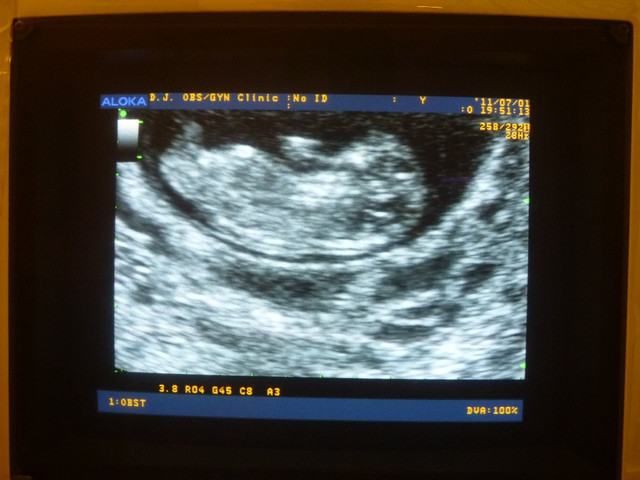

超音波螢幕下放大的小貝果

有人形出現了耶

手腳也出來了